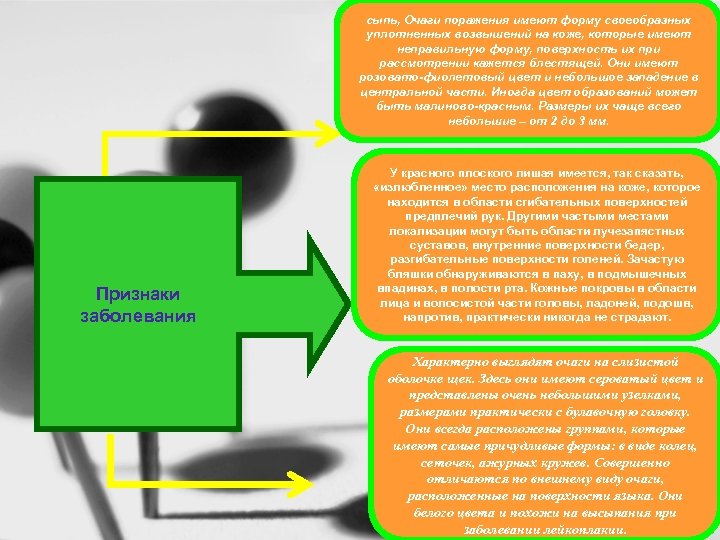

сыпь, Очаги поражения имеют форму своеобразных уплотненных возвышений на коже, которые имеют неправильную форму, поверхность их при рассмотрении кажется блестящей. Они имеют розовато-фиолетовый цвет и небольшое западение в центральной части. Иногда цвет образований может быть малиново-красным. Размеры их чаще всего небольшие – от 2 до 3 мм. Признаки заболевания У красного плоского лишая имеется, так сказать, «излюбленное» место расположения на коже, которое находится в области сгибательных поверхностей предплечий рук. Другими частыми местами локализации могут быть области лучезапястных суставов, внутренние поверхности бедер, разгибательные поверхности голеней. Зачастую бляшки обнаруживаются в паху, в подмышечных впадинах, в полости рта. Кожные покровы в области лица и волосистой части головы, ладоней, подошв, напротив, практически никогда не страдают. Характерно выглядят очаги на слизистой оболочке щек. Здесь они имеют сероватый цвет и представлены очень небольшими узелками, размерами практически с булавочную головку. Они всегда расположены группами, которые имеют самые причудливые формы: в виде колец, сеточек, ажурных кружев. Совершенно отличаются по внешнему виду очаги, расположенные на поверхности языка. Они белого цвета и похожи на высыпания при заболевании лейкоплакии.